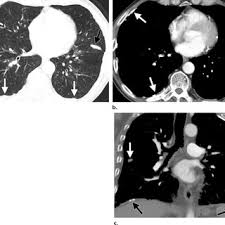

Asbestos Related Calcified Pleural Plaques Can Appear In Various Shapes Download Scientific Diagram

Asbestos Related Calcified Pleural Plaques Can Appear In Various Shapes Download Scientific Diagram from www.researchgate.net

Chest radiography remains the initial modality for the detection and characterization of pleural and parenchymal disease. There are innumerable pleural plaques, seen mostly en face. Department of radiology, university of british. Experience in the field of asbestos related radiological changes. Therefore, pulmonary fibrosis associated with pleural . Pleural plaques were defined as areas of pleural thickening. Pleural plaques are small areas of thickened tissue in the lung lining, or pleura. We concluded that asbestos related pleural plaques can under special.